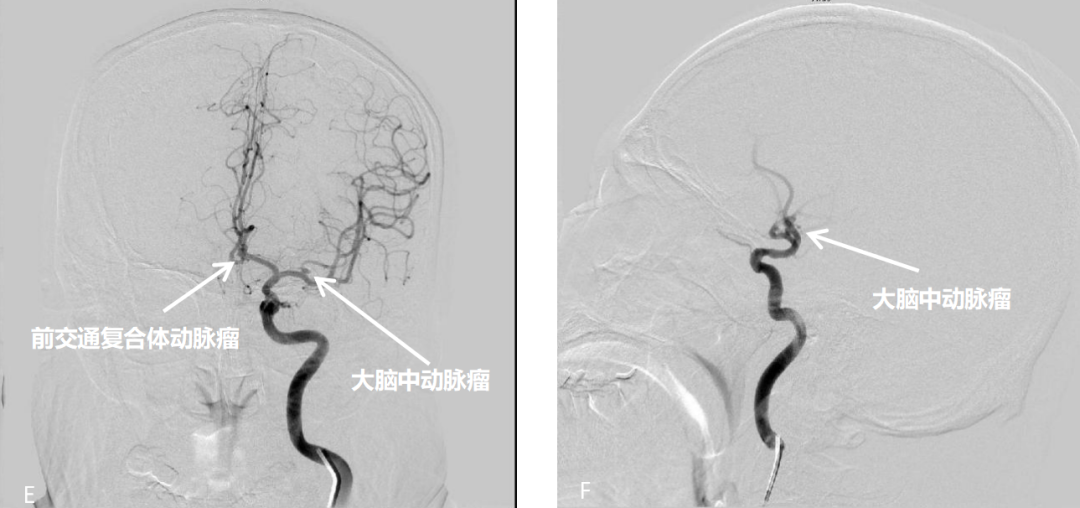

患者为小脑出血,入院后进一步行CTA及DSA检查发现左侧前交通复合体动脉瘤、左侧大脑中M1分叉部动脉瘤,小脑出血(2.5cm×2.8cm×2.4cm/2)为8.4ml,患者无神经功能恶化或脑干受压,根据2019年中国蛛网膜下腔出血指南“出现神经功能恶化或脑干受压的小脑出血者,无论有无脑室梗阻致脑积水的表现,都应尽快手术清除血肿(Ⅰ级推荐,B级证据);不推荐单纯脑室引流而不进行血肿清除(Ⅱ级推荐,C级证据)”[13],患者无蛛网膜下腔出血,结合动脉瘤位置[前交通动脉、大脑中动脉,破裂出血常在纵裂池、环池、鞍上池、四叠池、外侧裂以及相近的脑实质内(常位于幕上)]及小脑出血(幕下,位于小脑脑实质内)特点,小脑出血与动脉瘤无关,所以脑出血可选择保守治疗,密切观察患者的症状、体征、意识、瞳孔及复查CT结果,若有病情进展,可考虑手术。

患者为未破裂多发动脉瘤,若同时夹闭2个动脉瘤,对病人的手术体位、切口、动脉瘤的大小及形体、动脉瘤的指向、瘤颈宽度、载瘤动脉与周围血管、神经、骨性结构的关系及动脉管壁硬化钙化以及瘤颈处载瘤动脉有无分支血管、动脉瘤中有无穿支血管、血流动力学改变等均需考虑。分析患者为小型动脉瘤,形态不规则,指向不同,影像学未见明显钙化,但有同时夹闭可能。

患者56岁,且均为宽颈动脉瘤,小型动脉瘤,一个动脉瘤位于大脑中M1分叉部,根据指南“倾向于栓塞术的因素:年龄>70岁、不存在有占位效应的血肿、动脉瘤相关因素(后循环动脉瘤、窄颈动脉瘤、单叶形动脉瘤);倾向于推荐夹闭术的因素:年龄较轻、合并有占位效应的血肿、动脉瘤相关因素(大脑中动脉及胼周动脉瘤、瘤颈宽、动脉瘤体直接发出血管分支、动脉瘤和血管形态不适于血管内弹簧圈栓塞术)(Ⅱ级推荐,C级证据)”[13]。